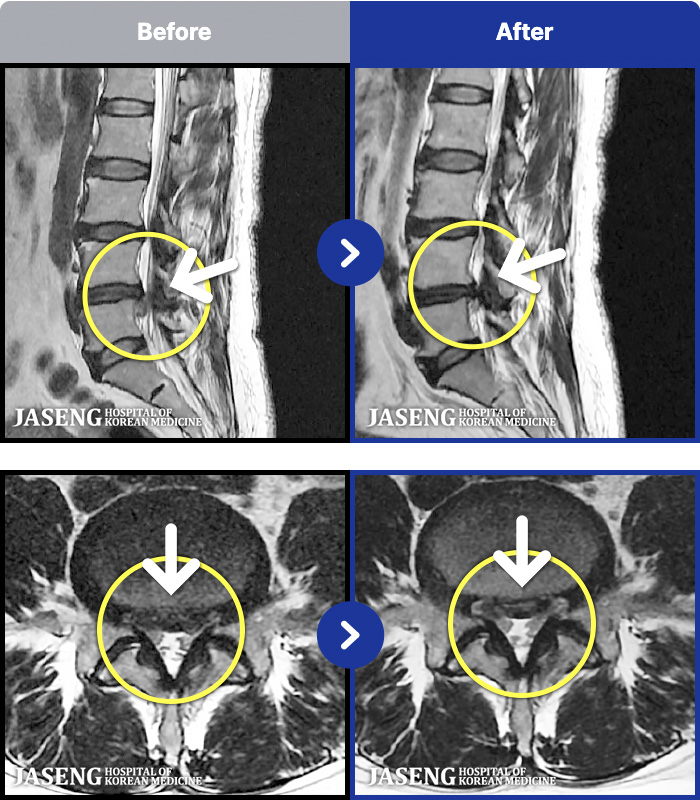

MRI ġ

88 MRI ũ ʸ Ȯϼ.

㸮 ؼ ̱ ư ϴ.